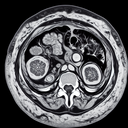

МРТ нирок

МРТ (магнітно-резонансна томографія) нирок — це неінвазивний метод обстеження, який використовує магнітні поля та радіохвилі для створення детальних зображень нирок та навколишніх тканин. Це дослідження призначене для: 1. Оцінки анатомії нирок...